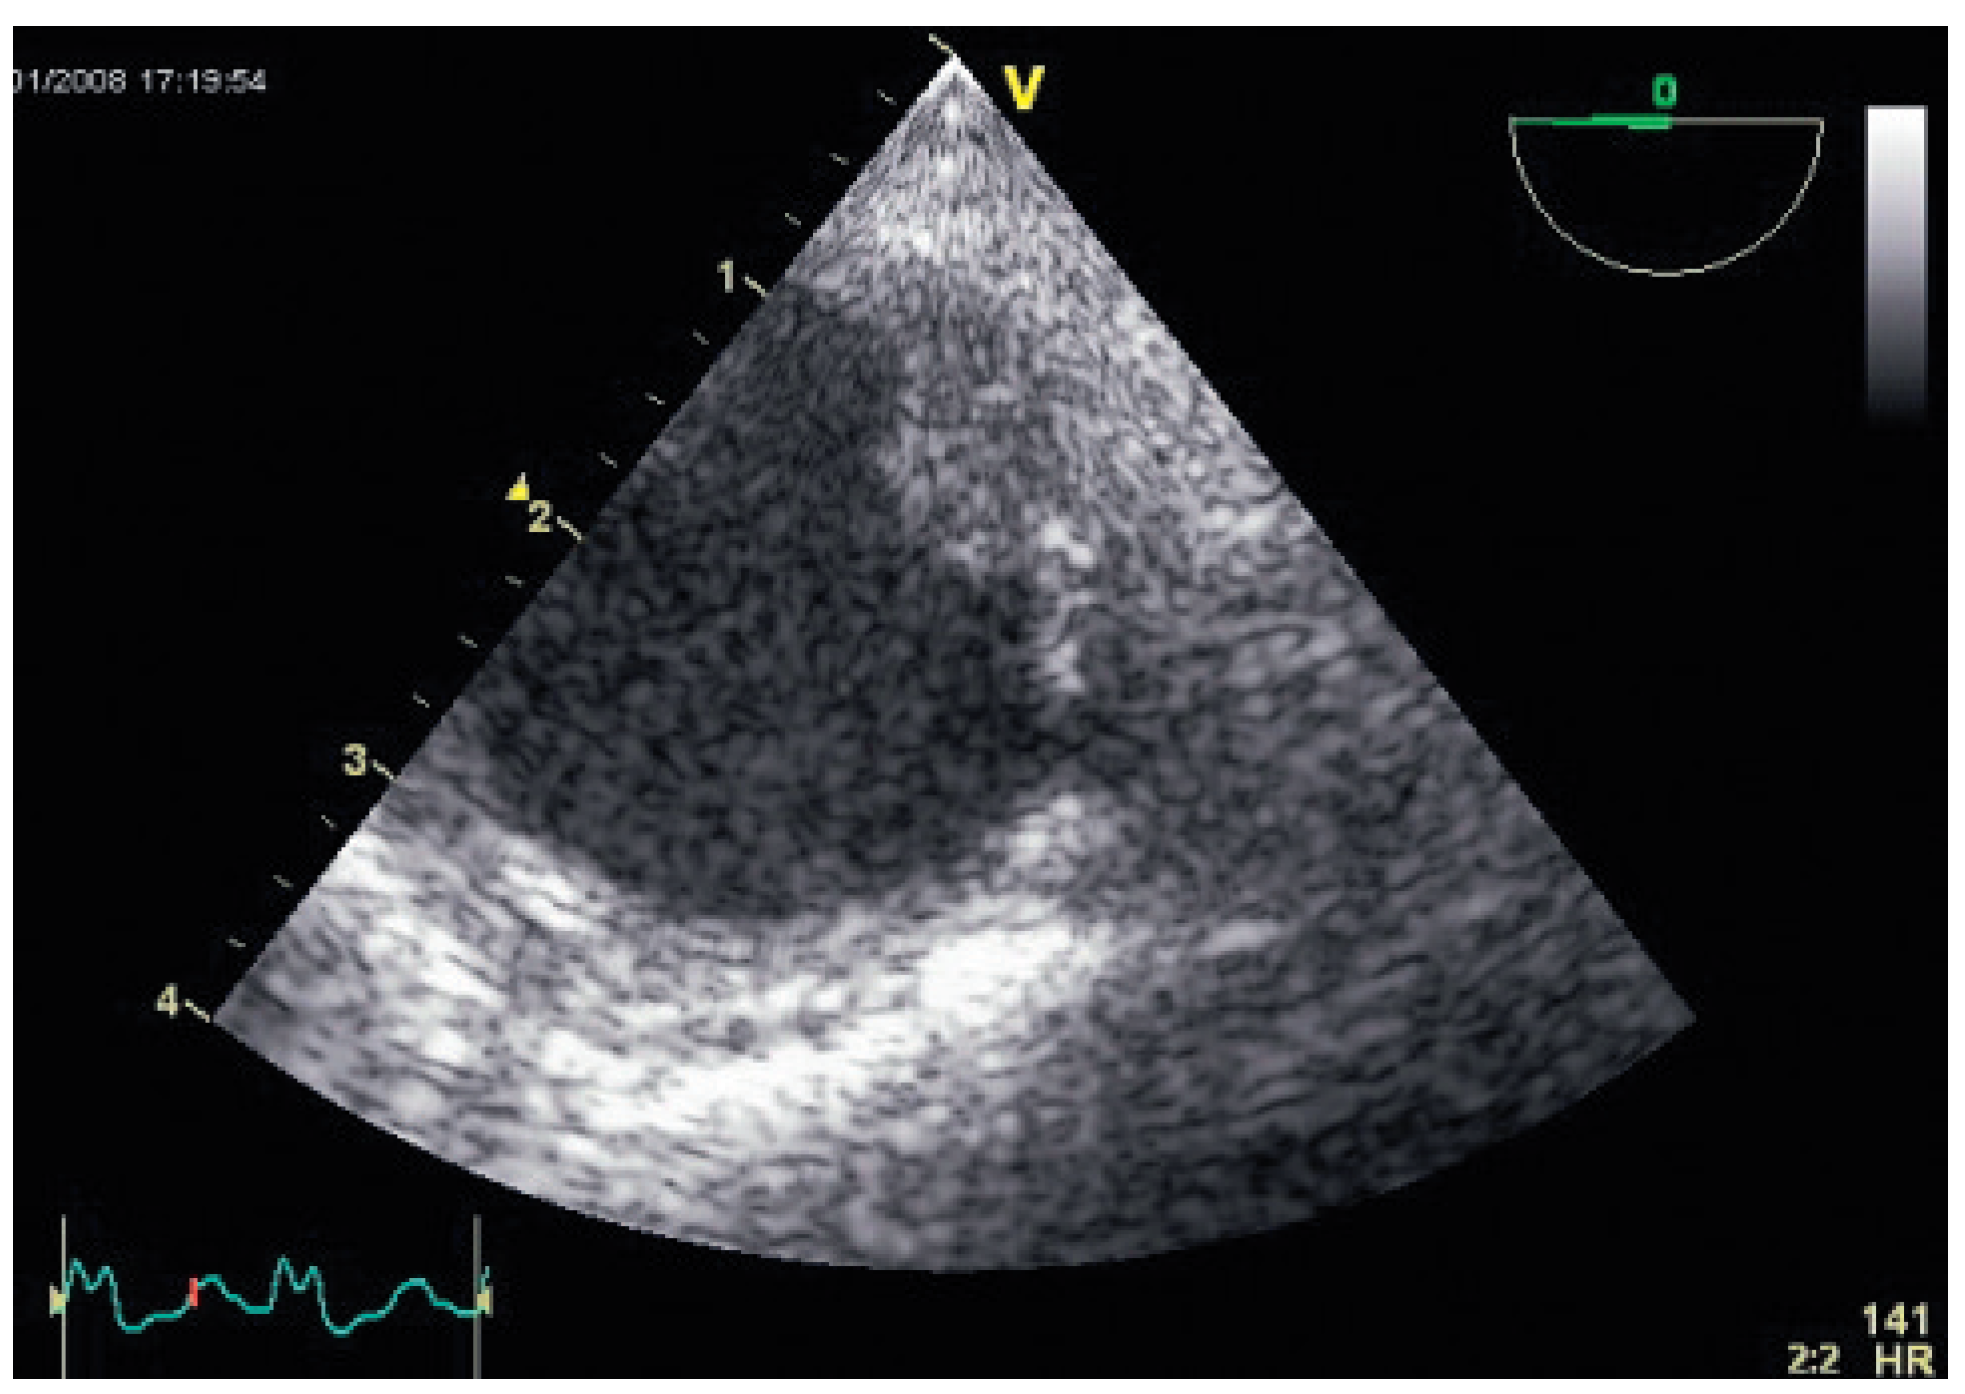

Flottierender Thrombus in der Aorta Descendens